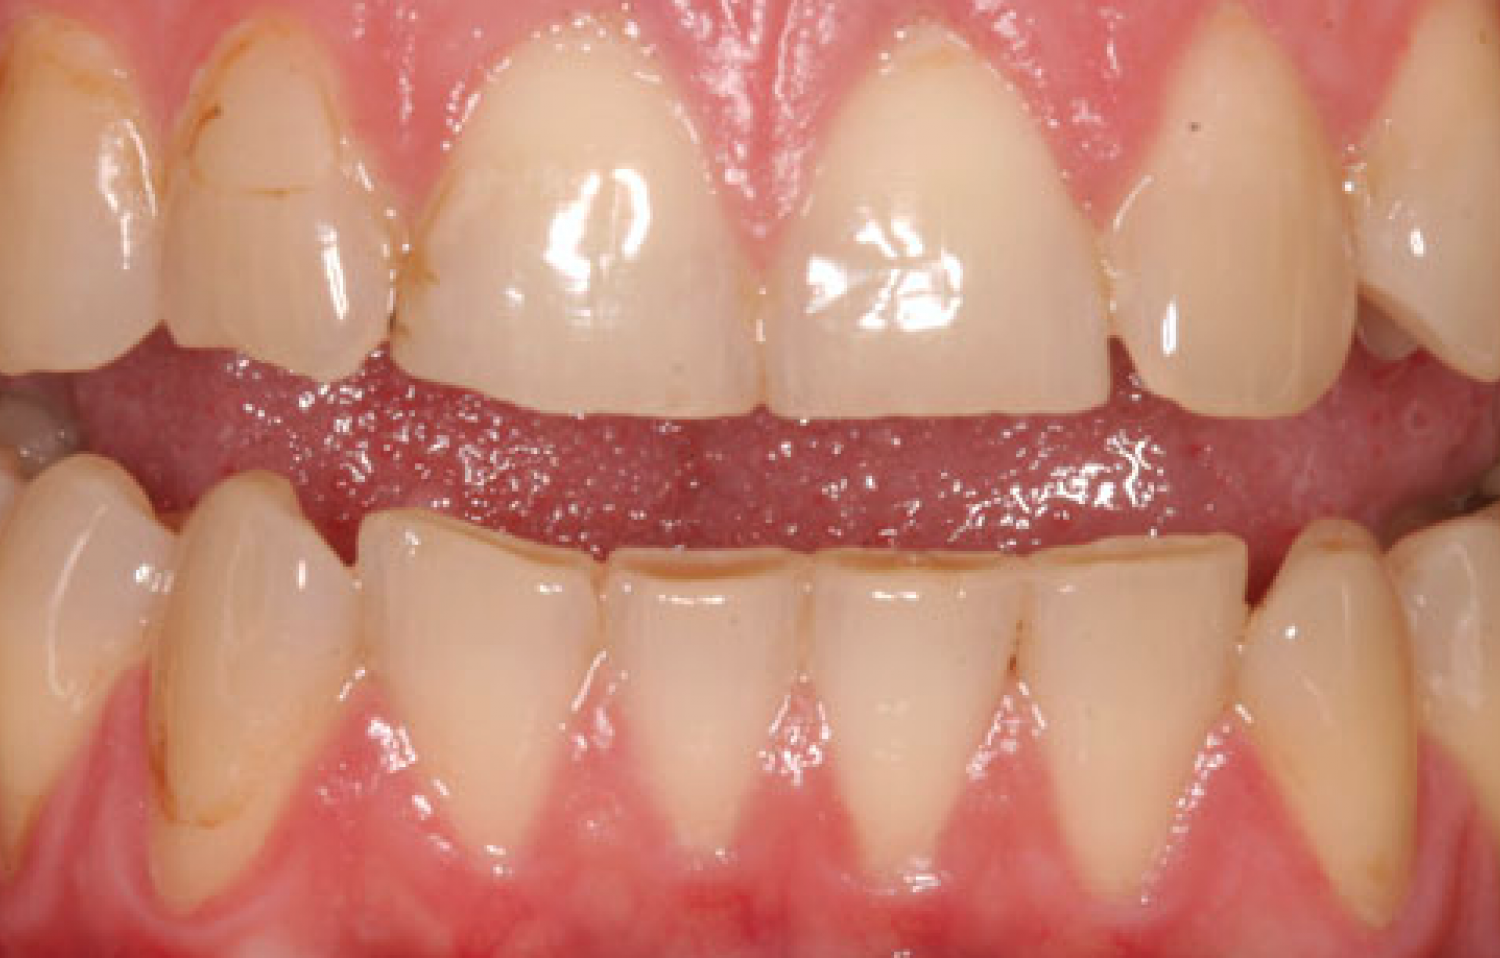

The following 2 photos* illustrate the increased added length and new look. Both the upper 6 and lower 6 teeth were treated.

| Before Dahl Build-ups | After Dahl build-ups |